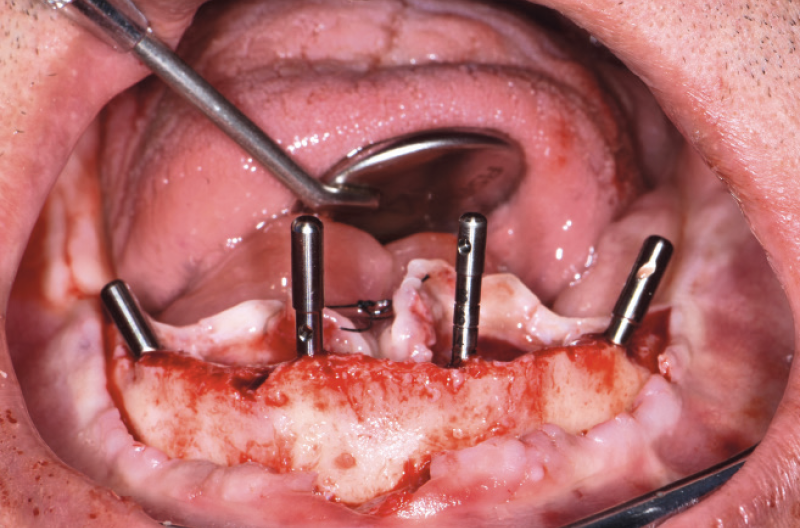

NellŌĆÖarcata inferiore ho posizionato distalmente 2 impianti Max Stability ├ś 3,75 mm L 12 e L 14 mm inclinati (ŌĆ£tiltatiŌĆØ) davanti ai forami mentonieri secondo il protocollo All-on-four, mentre nella zona sinfisaria ho inserito 2 impianti Narrow ├ś 2,9 L 12 mm (Figg. 15-20).

Fig. 18 – Inserimento degli impianti Narrow 2.9

Fig. 19 – Inserimento degli impianti distali tiltati

Fig. 20 – Vista dei 4 impianti inseriti nellŌĆÖinferiore